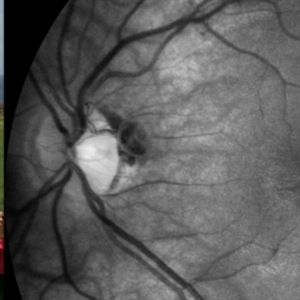

VHL "Free Floating" Juxtapapillary Hemangioblastoma

Jul 1 2014 by John S. King, MD

30-year-old female with fhx VHL and CNS hemangioblastomas and visceral lesions. P/C with a floater (no PVD or VH) after episodes of vomiting.

Photographer: Wayne A Ladlee Jr

Imaging device: Red Free

Condition/keywords: retinal hemangioblastoma, Von Hippel-Lindau